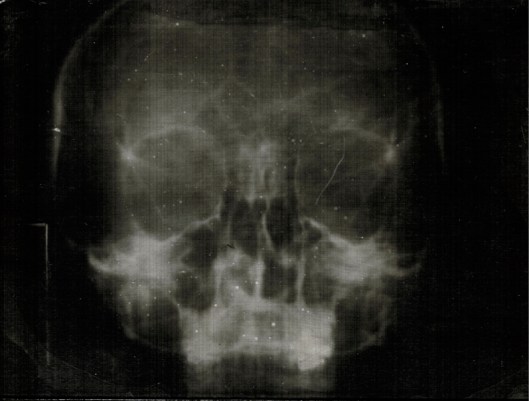

A loved one recently underwent a few medical procedures. Thankfully, the news was good, but it caused me to wonder what the medical world would be like if our x-rays were made with wet plate collodion.

Since the collodion process is said to reveal our true character, how would our diagnosis change in a world of wet plate collodion x-rays?

Your test results are in. Looks like you’ve got a severe case of …